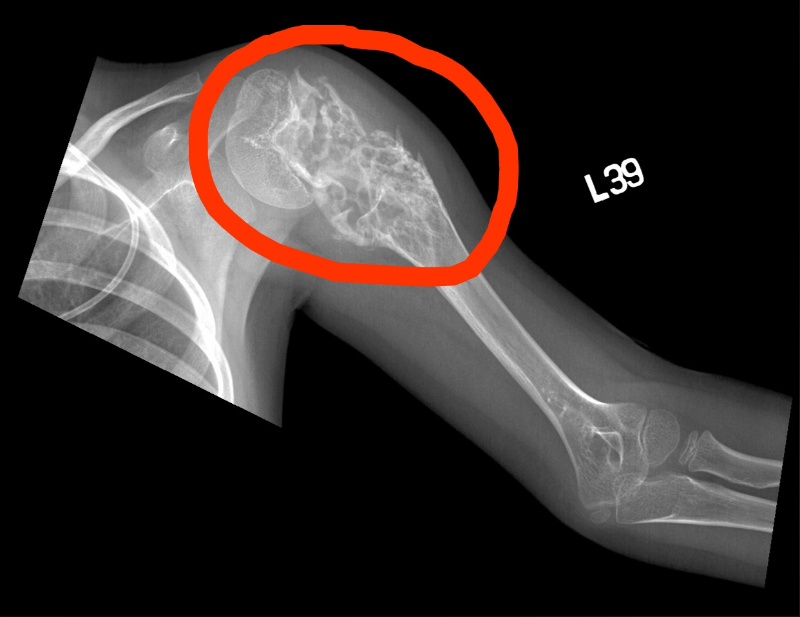

| Компьютерная томография (КТ) или магнитно-резонансная томография (МРТ) | Помогают получить детальные послойные изображения опухоли, оценить ее связь с окружающими тканями, состояние сосудов и второй почки. КТ грудной клетки обязательно проводится для исключения метастазов в легких. |

- IV стадия: Наличие отдаленных метастазов (чаще всего в легких, реже — в печени, костях, головном мозге).